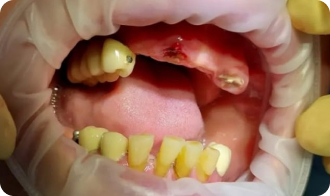

Установка All-on-4

До приёма:

• Полная адентия зубов

• Атрофия костной ткани

Результат:

• Установка имплантов Osstem

• Костная пластика

Срок: 2 дня